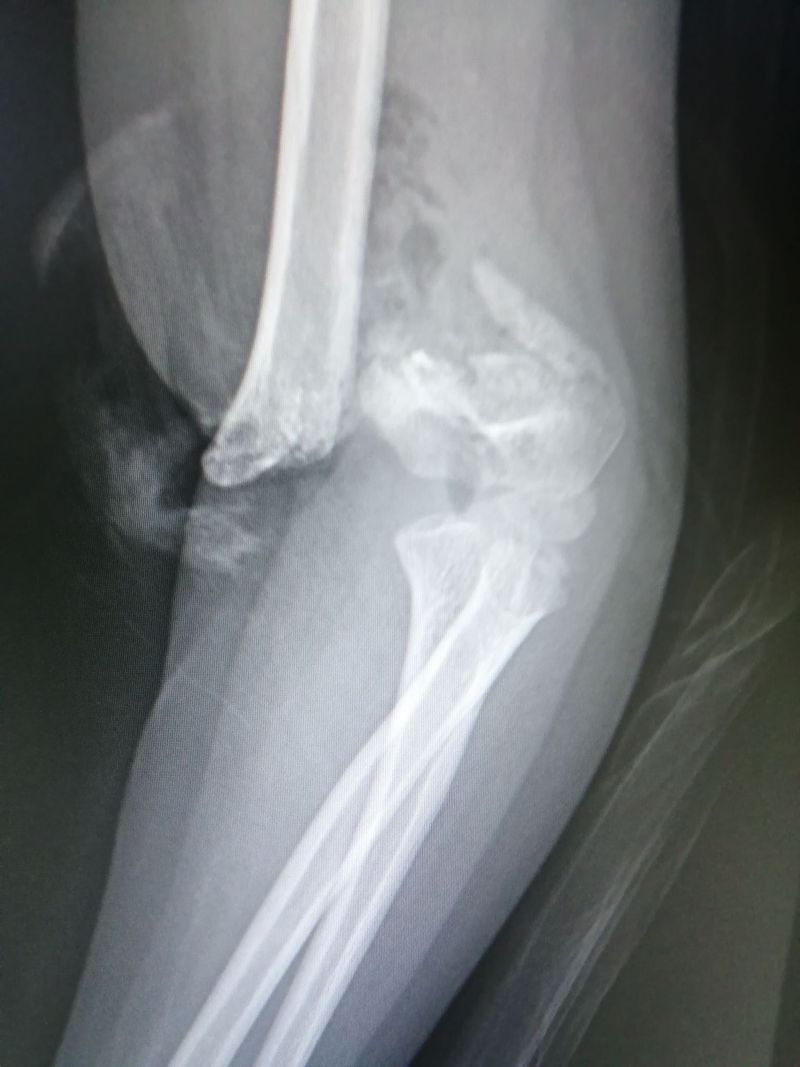

AP View

Left Humeral Supracondylar Fracture.

Fracture

Elbow

Left

Supracondylar